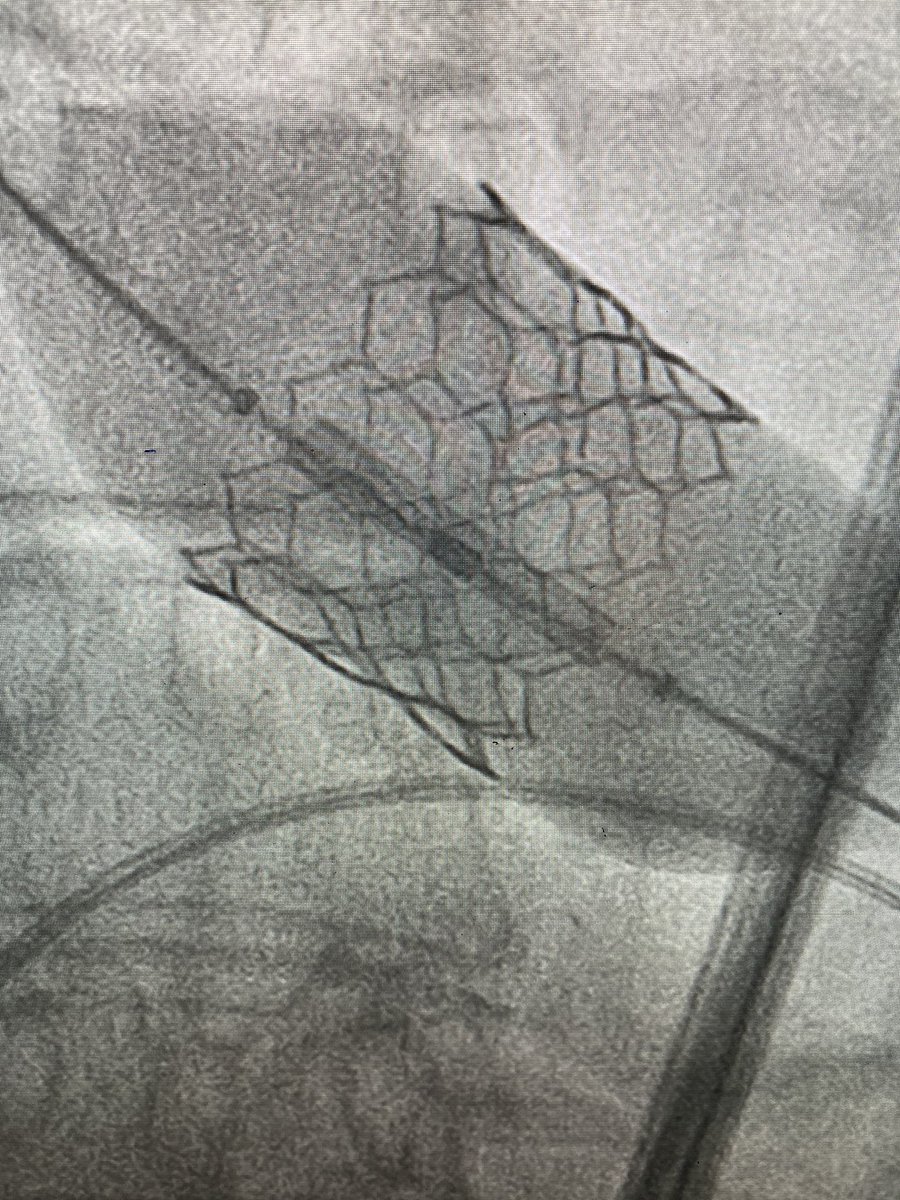

Our first #Sapien3Ultra #TAVR on the @Edwards_TAVR Commander system @MountSinaiNYC @MountSinaiHeart. Annular/LVOT Ca no PVL! Outstanding team! @KHERA_MD Samin Sharma, Annapoorna Kini, Stam Lerakis.